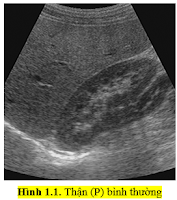

1. Hình ảnh thận bình thường.